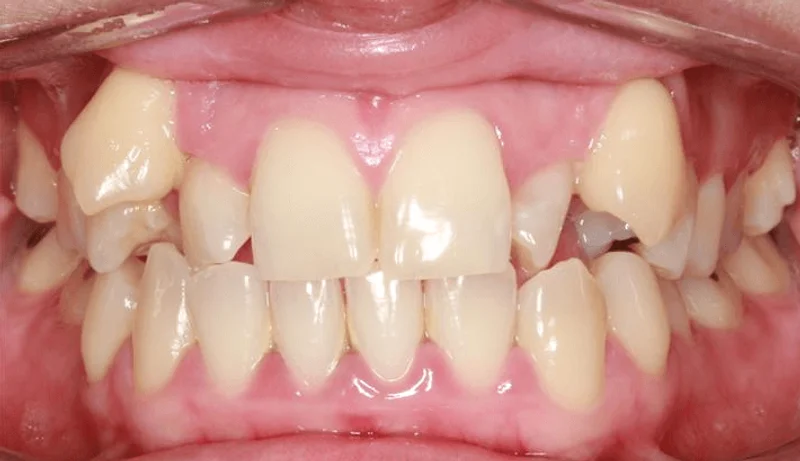

Center Bite

Center Bite - Before Treatment

Before